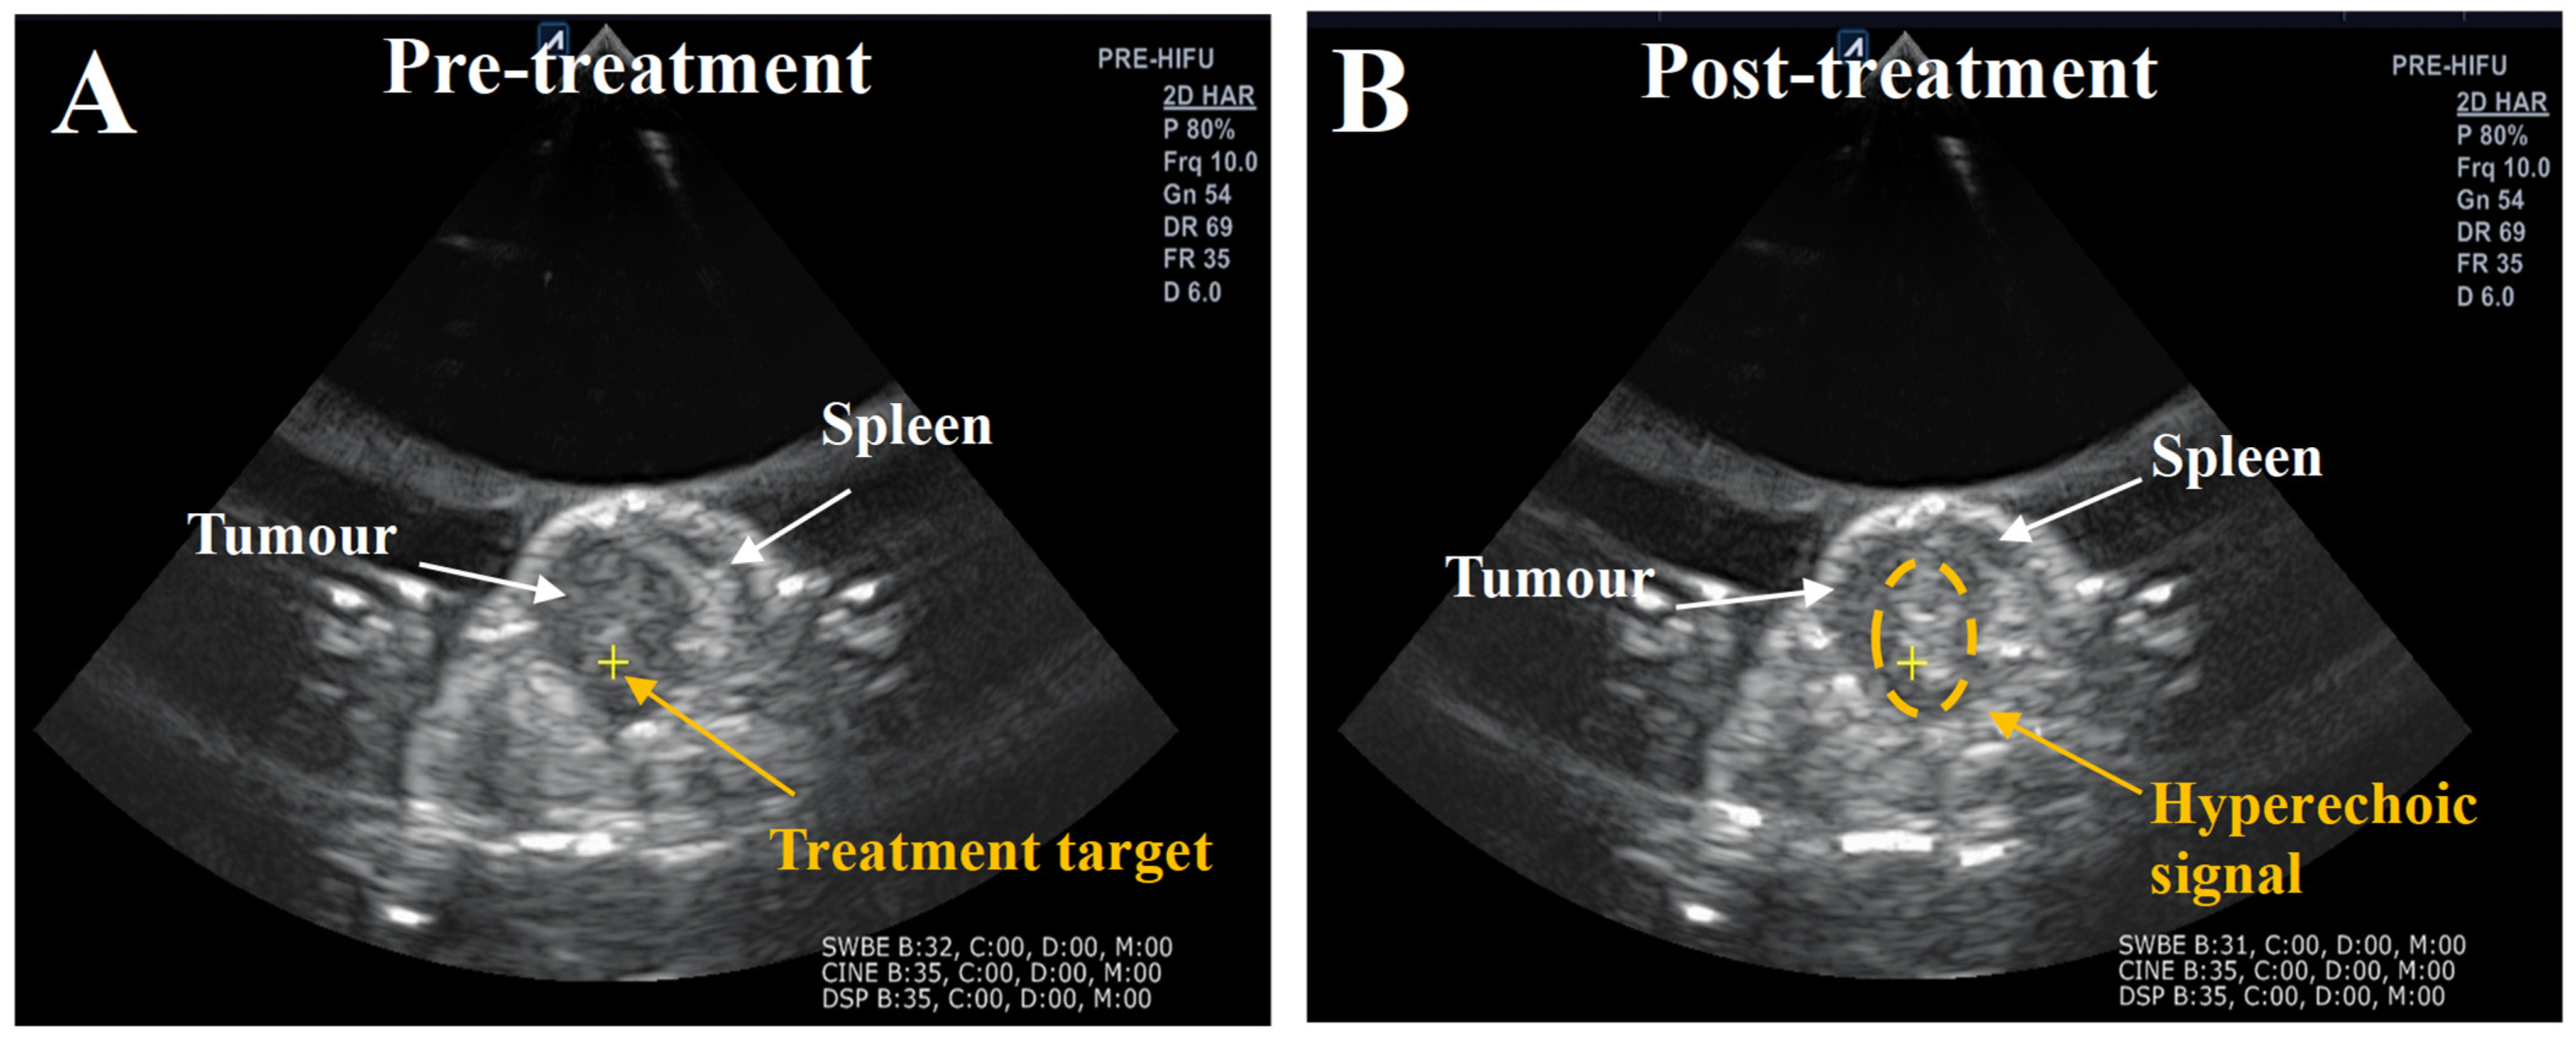

| Subject | Number of Exposure Positions per Tumour | Number of Exposure Pulses per Tumour | Percentage of HH-Positive Exposure Pulses (%) | Number of HH Positive Exposure Pulses per Tumour | Percentage of Broadband Signal Exposure Positive Pulses (%) | Number of Broadband-Positive Exposure Pulses per Tumour | Hyper-Echoic Signals |

| BH- Subject 1 | 28 | 660 | 98 | 650 | 14 | 95 | Yes |

| BH 2- Subject 2 | 17 | 350 | 100 | 350 | 94 | 330 | Yes |

| BH 3- Subject 3 | 30 | 720 | 100 | 720 | 20 | 150 | In-conclusive |

| BH 4- Subject 4 | 19 | 450 | 100 | 450 | 77 | 345 | Yes |

| BH 5- Subject 5 | 25 | 535 | 100 | 535 | 67 | 360 | Yes |

| Comb 1- Subject 1 | 13 | 310 | 97 | 300 | 100 | 310 | Yes |

| Comb 2- Subject 2 | 10 | 230 | 91 | 210 | 95 | 220 | Yes |

| Comb 3- Subject 3 | 22 | 530 | 100 | 530 | 4 | 20 | Yes |

| Comb 4- Subject 4 | 17 | 350 | 100 | 350 | 2 | 6 | Yes |